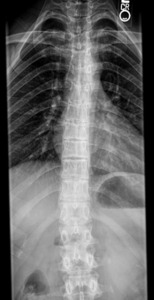

Delving further into her history revealed that she was originally diagnosed with hEDS by a prior chiropractor in 2015 as a result of examination findings which met the Beighton and Villefranche criteria. Repeated shoulder dislocations had led to the need for labral repair and shoulder stabilization surgery (bilateral surgeries in 2015 and 2019). She saw a rheumatologist in 2020 for joint pain and was further diagnosed with Hypermobile, Classical, Cardiac-Valvular, and Arthrochalasic types of EDS. Comorbid conditions of POTS and Raynaud’s syndrome were also diagnosed. She was referred for head and upper cervical MRI with and without contrast to rule out tumors or other lesions in the brain and brain stem. MRI revealed a mild Chiari Type 1 malformation but was otherwise clear of lesions. Radiographs were taken of the hands, feet, knees, lumbar spine, and pelvis. The patient was diagnosed with juvenile idiopathic arthritis and spina bifida occulta of L5 and S1 along with hyperlordosis of the lumbar spine, demonstrated in Figures 1 and 2.

Additional radiographs were taken in 2022 after she was involved in a motor vehicle accident (figures 3 and 4). The accident provoked further low back and migraine symptoms while creating numbness and radicular symptoms in her right leg. Additional diagnoses were made of Schuermann’s disease and kyphoscoliosis, with a right curvature from T6-L2.